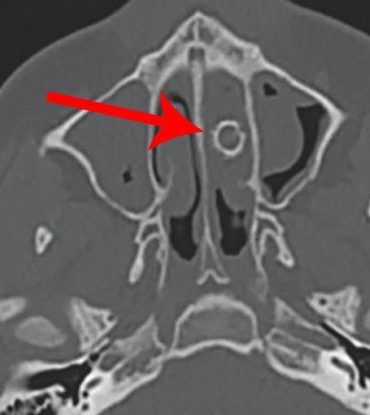

A teen who had experienced years of nasal congestion along with a mysterious “foul odor” when he blew his nose...

A woman in Taiwan unknowingly had two chopstick fragments lodged in her sinuses for a week after a violent fight...